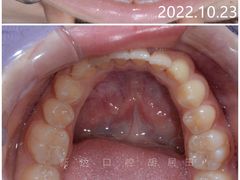

番茄宝妈 | 22-10-23

报错

• -新达口腔(华东理工大学店)